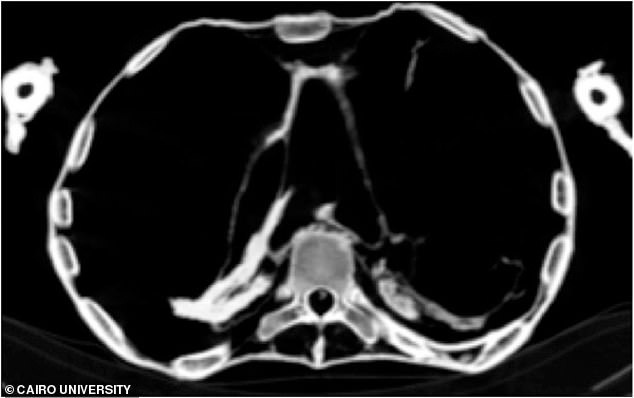

Các nhà Ai Cập học từ Đại học Cairo (Ai Cập) đã sử dụng kỹ thuật CT scan để tìm ra nguyên nhân cái chết và tư thế đầy đau khổ của người đàn bà Ai Cập cổ đại và phát hiện ra rằng nàng đã qua đời vì một cơn đau tim cấp. Tình trạng xơ vữa động mạch vẫn thể hiện khá rõ nhờ kỹ thuật ướp xác danh tiếng của người Ai Cập cổ đại.

Các hình ảnh CT scan cho thấy "công chúa la hét" bị một cơn đau tim cấp do xơ vữa động mạch lâu ngày - ảnh: Đại học Cairo